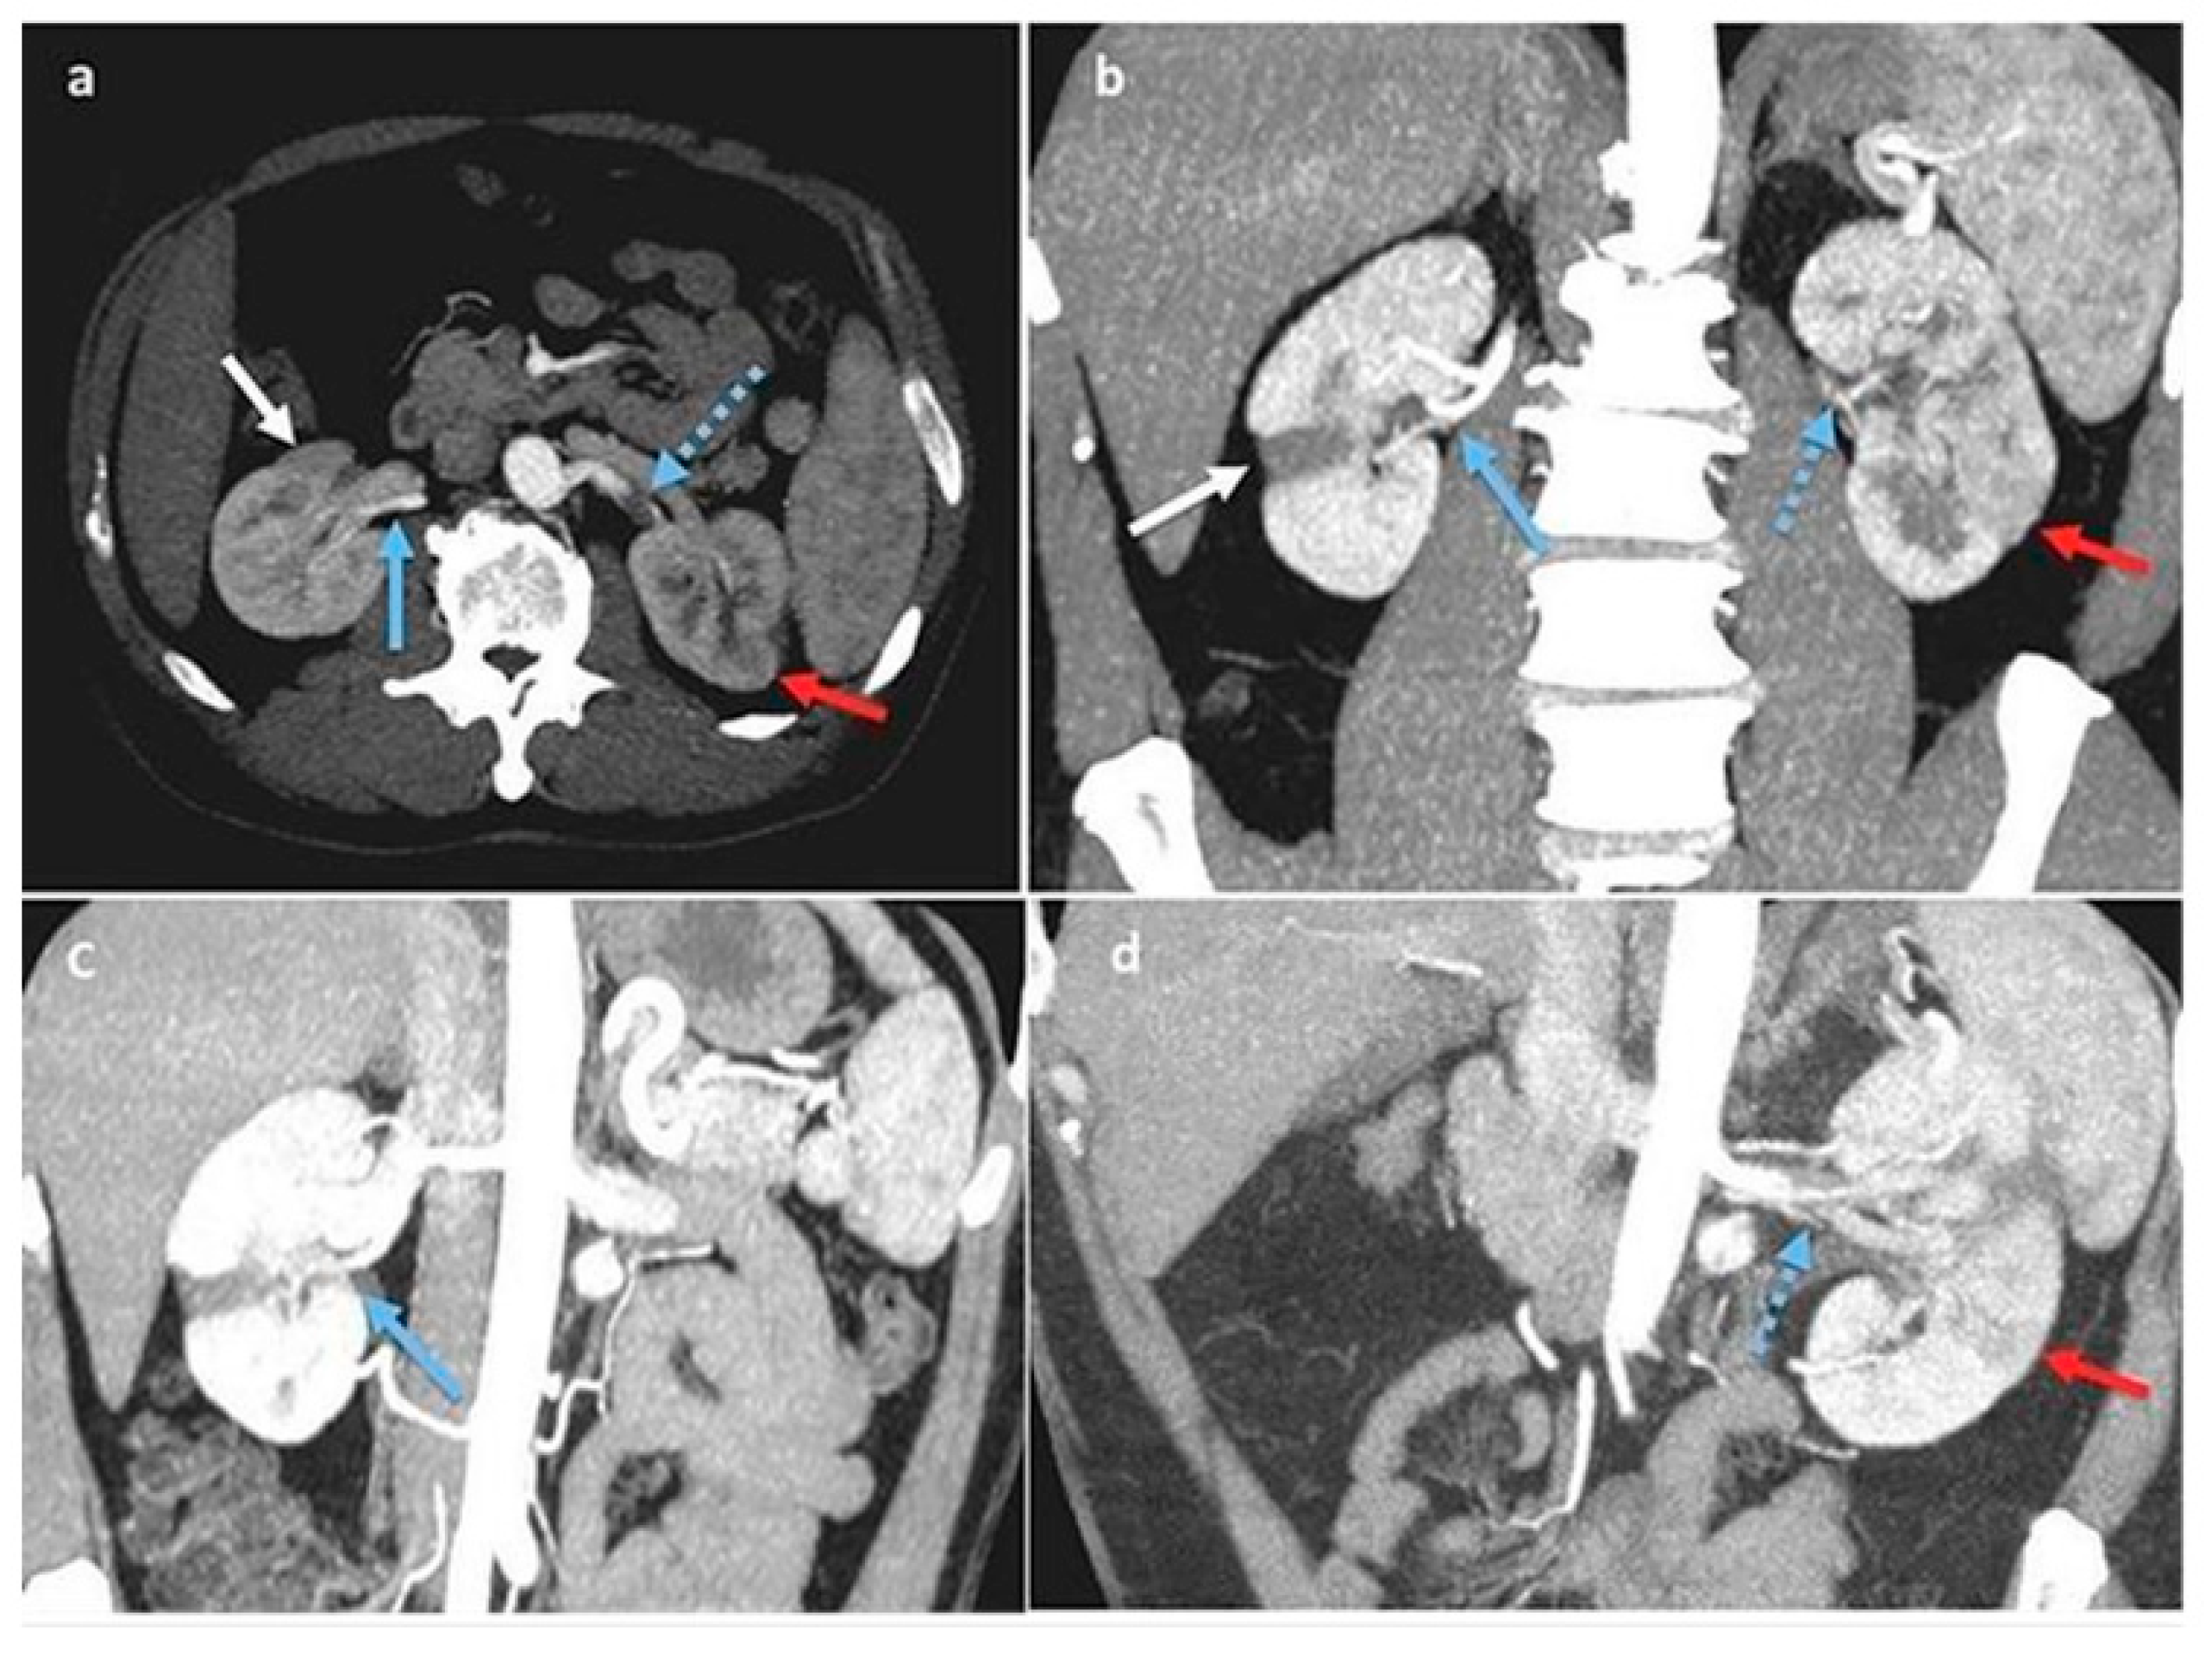

Two days later, a contrast-enhanced complete abdomen computed tomography (CT) scan was conducted [1]. This revealed multiple infarctions and ischemic areas with hypoperfusion in the upper middle third of the left kidney and in a large area of the middle and lower right kidney; the left renal artery exhibited increased intimal thickening and arteritis, similar to thrombotic events, resulting in an extremely narrow residual lumen. The multiplanar reconstruction revealed bilateral renal artery dissection and multiple arterial infarctions disseminated throughout both kidneys (Figure 1a–d).

Figure 1.

(a–d): Multiplanar reconstructions on Anglo-CT scan, arterial phase. Right kidney: focal ischemic area (white arrow) associated with sub-acute dissection of the inferior polar artery (blue arrow). Left kidney: acute dissection of renal artery (blue arrow with dots) with focal acute ischemic area (red arrow).